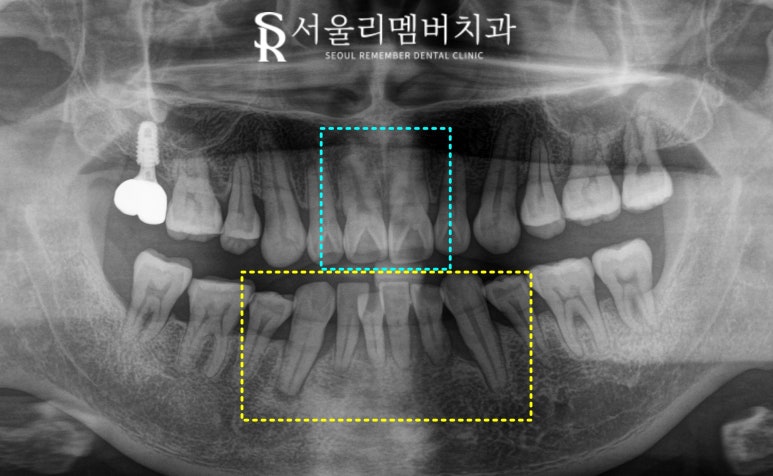

아래 앞니 부위의 33번(좌측 송곳니)부터

43번(우측 송곳니)까지

총 6개의 하악 전치부에 동요도가 존재했는데요,

치주 질환으로 잇몸뼈가 녹고,

치근을 잡아주는 치주 인대가 녹으면서

흔들림이 생긴 겁니다.

2024.11.16

엑스레이를 찍어보니

뿌리 주변으로 까맣게 골소실이 나타나고 있습니다.